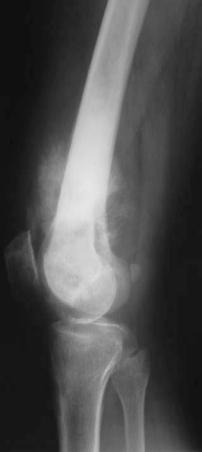

临床与病理:1、年龄:20-40岁,约65%;2、部位:长管状骨骨端,膝关节附近居多

3、病理: I级:良性;II级:潜在恶性;III级:恶性

X线表现:① 多数为偏心性骨破坏 (溶骨型)② 局部骨 膨胀性,骨皮质变薄形成薄层骨壳,无硬化边③ 大小不一的分隔小房呈肥皂泡状, 并见骨嵴。

④ 无骨膜反应,⑤一般不穿破关节软骨

I级GCT

II级GCT

桡骨远端偏侧性膨胀性骨质破坏,中有骨嵴。

II~III级GCT

巨细胞瘤恶性变